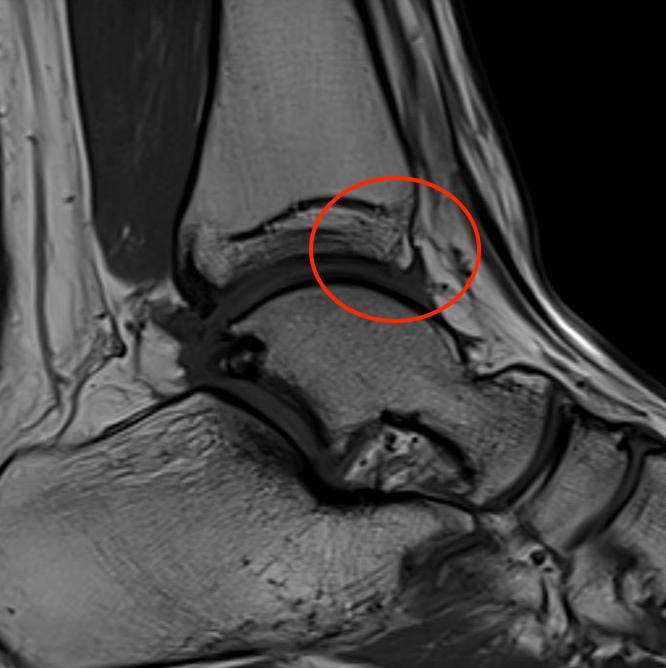

Impingement between anterior distal tibial osteophyte and sulcus of the talus in dorsiflexion

Anterior tibial and talus spurs with normal joint space

MRI